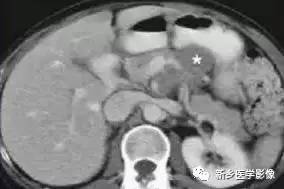

四、胰腺转移瘤

胰腺转移瘤在临床上较为少见, 1000 例恶性肿瘤尸检中,仅3 %有胰腺转移。原发肿瘤可为肺癌、乳腺癌、肾细胞癌、卵巢癌、结肠癌、黑色素瘤等。胰腺不是肿瘤转移的常见部位。胰腺转移瘤的影像学表现与原发肿瘤有一定关系, 可表现为乏血供或富血供胰腺肿块, 有时E RCP 可示主胰管内充盈缺损。转移

瘤的影像学表现少有特异性,且发病率很低,故诊断常依靠原发肿瘤的确诊以及胰腺病变的细胞学检查。